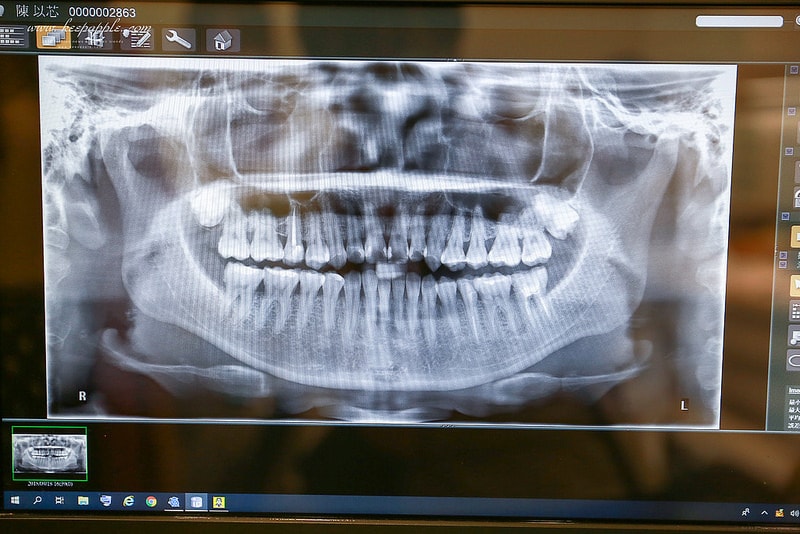

「X光室」使用的是近幾個月出的 Veraview X800 斷層掃描儀

這可是全台第一、二家進的機器

在台灣只有兩家有 (另一台在台北)

精準度比一般的還高

我覺得這超厲害的!!!

這次是要來做隱適美的事前功課

諮詢之前會先到X光室拍攝

再和醫師討論之後需要的療程

運用最新尖端的設備

能更精準地了解客人想改善的地方